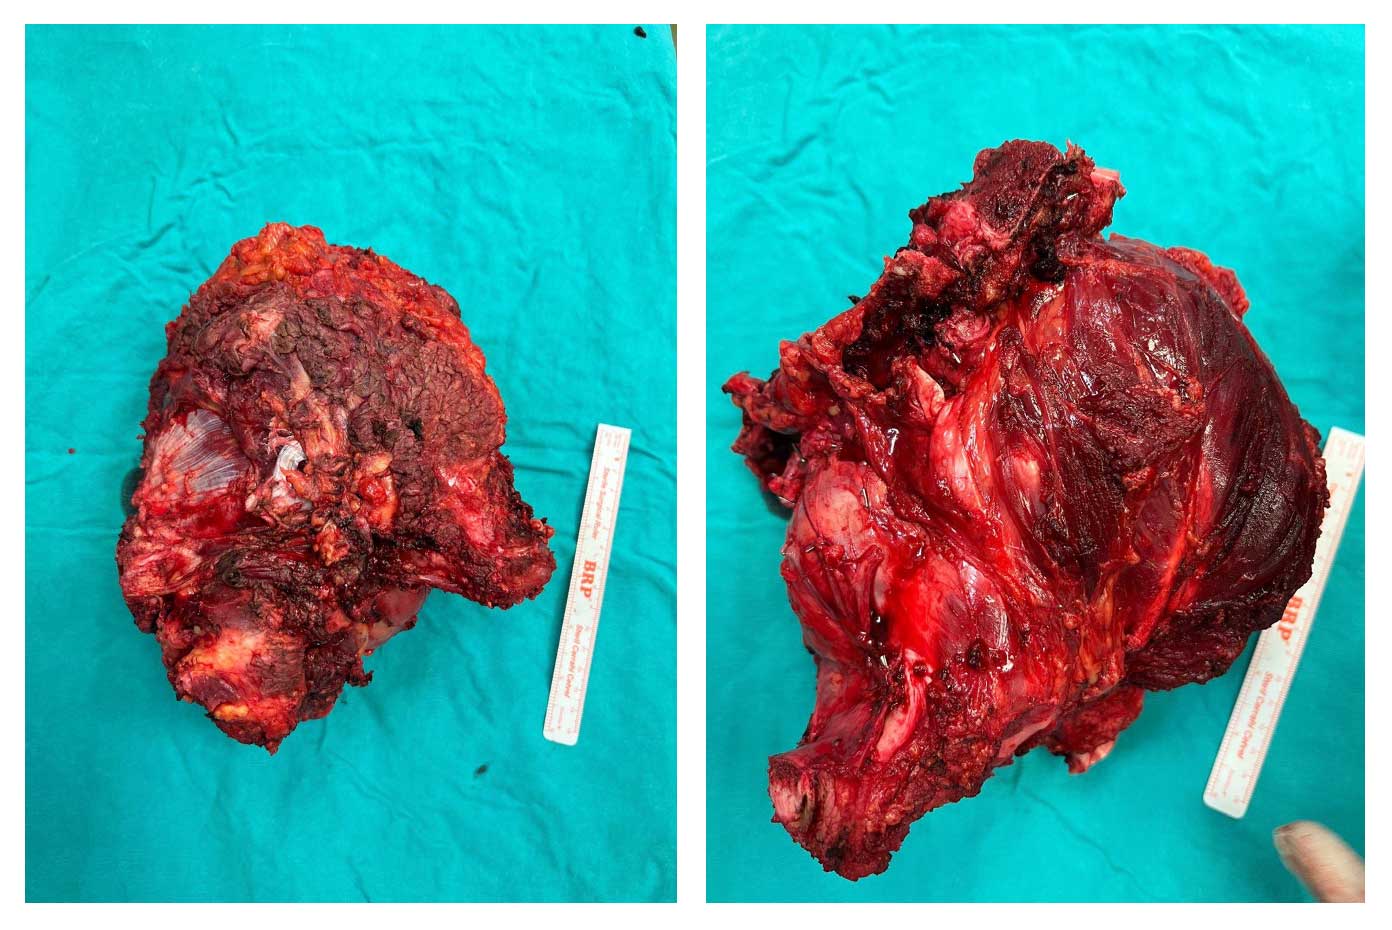

Ameliyat Esnası: Çıkarılan tümör dokusunun klinik görüntüsü.